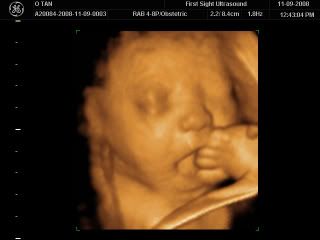

Here's a picture of him rubbing the back of his hand against his lips and a few times he even sucked on it! Super cute!